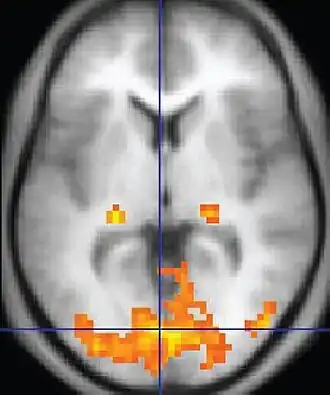

An fMRI image with yellow areas showing increased activity compared with a control condition

Functional magnetic resonance imaging or functional MRI (fMRI) measures brain activity by detecting changes associated with blood flow.[1][2] This technique relies on the fact that cerebral blood flow and neuronal activation are coupled. When an area of the brain is in use, blood flow to that region also increases.[3]

The primary form of fMRI uses the blood-oxygen-level dependent (BOLD) contrast,[4] discovered by Seiji Ogawa in 1990. This is a type of specialized brain and body scan used to map neural activity in the brain or spinal cord of humans or other animals by imaging the change in blood flow (hemodynamic response) related to energy use by brain cells.[4] Since the early 1990s, fMRI has come to dominate brain mapping research because it does not involve the use of injections, surgery, the ingestion of substances, or exposure to ionizing radiation.[5] This measure is frequently corrupted by noise from various sources; hence, statistical procedures are used to extract the underlying signal. The resulting brain activation can be graphically represented by color-coding the strength of activation across the brain or the specific region studied. The technique can localize activity to within millimeters but, using standard techniques, no better than within a window of a few seconds.[6] Other methods of obtaining contrast are arterial spin labeling[7] and diffusion MRI. Diffusion MRI is similar to BOLD fMRI but provides contrast based on the magnitude of diffusion of water molecules in the brain.